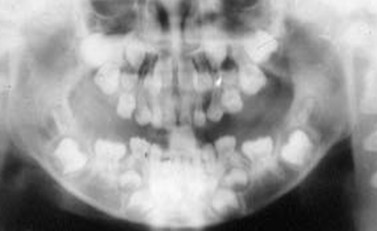

解析: 先天性无牙畸形 Total Anodontia

先天性无牙畸形的病因:外胚叶发育不全综合症、遗传性疾病。其临床表现:无汗、少汗、毛发稀疏、乳恒牙均可缺失、牙齿稀疏、牙形小、圆锥状。治疗:活动义齿修复。